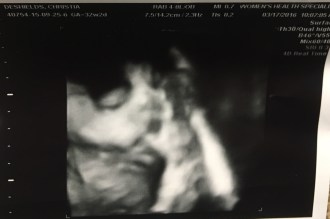

It’s been several months since we’ve chatted and if you haven’t heard yet, We are growing again! I am 37 weeks pregnant with baby number two and this pregnancy has been quite a doozy! But first, a funny story. When I announced my pregnancy several months ago at our monthly staff meeting at work, instead of saying my husband and I will be busy with two babies, I said my husband and I were busy, and now I’m pregnant….not in those exact words, but that’s how it came across lol. So needless to say, I was embarrassed that my baby brain had kicked in so sooner than before. Baby #2 doesn’t have a name quite yet, but we are working on it. His ETA is May 10th and this weekend we thought he was going to make an early arrival, but he changed his mind:). I had contractions all weekend and then all of a sudden they stopped!